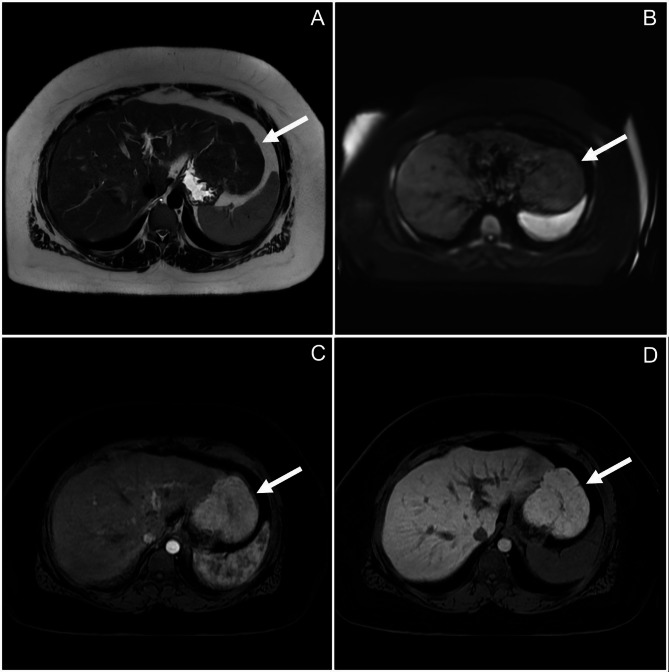

Case presentation: We describe a 33-year-old female who underwent excision of a pedunculated FNH. On gross examination, the lesion was lobular and vascular with homogenous tan-brown surfaces. Histological examination showed loss of normal liver architecture, abnormal intervening fibrous tracts, dysplastic arteries, and focal steatosis. Immunohistochemical staining with glutamine synthetase resulted in a branching, or "map-like" pattern. These findings were consistent with focal nodular hyperplasia. One of the most sensitive imaging techniques for diagnosing this lesion involves magnetic resonance imaging (MRI) with contrast, which discloses a homogenous mass that is hyperintense during the arterial phase with gradual decrease in intensity during the venous and equilibrium phases. The central stellate scar will often remain hyperintense for a prolonged period of time. On histology, normal hepatic architecture is lost to abnormal fibrotic bands and a characteristic stellate scar. Immunohistochemistry with glutamine synthetase uniquely highlights a map-like pattern that is not seen in other liver lesions.